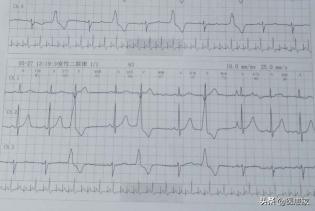

Tous les types de maladies cardiaques conduisent inévitablement à deux conditions : une activité électrique instable ou perturbée du cœur (arythmie) et une activité mécanique altérée du cœur (insuffisance cardiaque).

1. douleur thoracique nocturne.Chez les patients souffrant d'une maladie coronarienne, il existe non seulement la manifestation typique de l'angine d'effort, mais aussi, dans certains cas, une angine nocturne spontanée. Ce type de patients, la nuit en raison du spasme de l'artère coronaire, peut apparaître dans l'état de repos de la douleur thoracique, et la durée est plus souvent, commun dans le tabagisme et d'autres patients, l'électrocardiogramme de la douleur thoracique était l'élévation du segment ST performance. Dans ce cas, le diltiazem en gélules à libération prolongée peut être pris au coucher et donner de meilleurs résultats.

2. difficulté à respirer la nuit.Certains patients souffrant d'insuffisance cardiaque peuvent présenter des paroxysmes nocturnes de dyspnée dus à la position du corps, à l'augmentation du flux sanguin de retour et à l'excitation vagale. Certains patients souffrant de maladies respiratoires peuvent également présenter une oppression thoracique, qui doit être différenciée du BNP/NT-proBNP et de l'échographie cardiaque.

4. insuffisance cardiaque gauche aiguë.Chez certains patients souffrant d'une maladie coronarienne, la nuit, en particulier la fin de la nuit, est la période la plus propice aux épisodes d'insuffisance cardiaque, et une insuffisance cardiaque gauche aiguë peut survenir dans les cas graves, voire menacer le pronostic vital.

5. autres.Chez les patients souffrant d'une maladie cardiaque, des arythmies telles que des palpitations et des battements de cœur rapides peuvent également être présentes, qui sont généralement clarifiées par un électrocardiogramme ambulatoire.